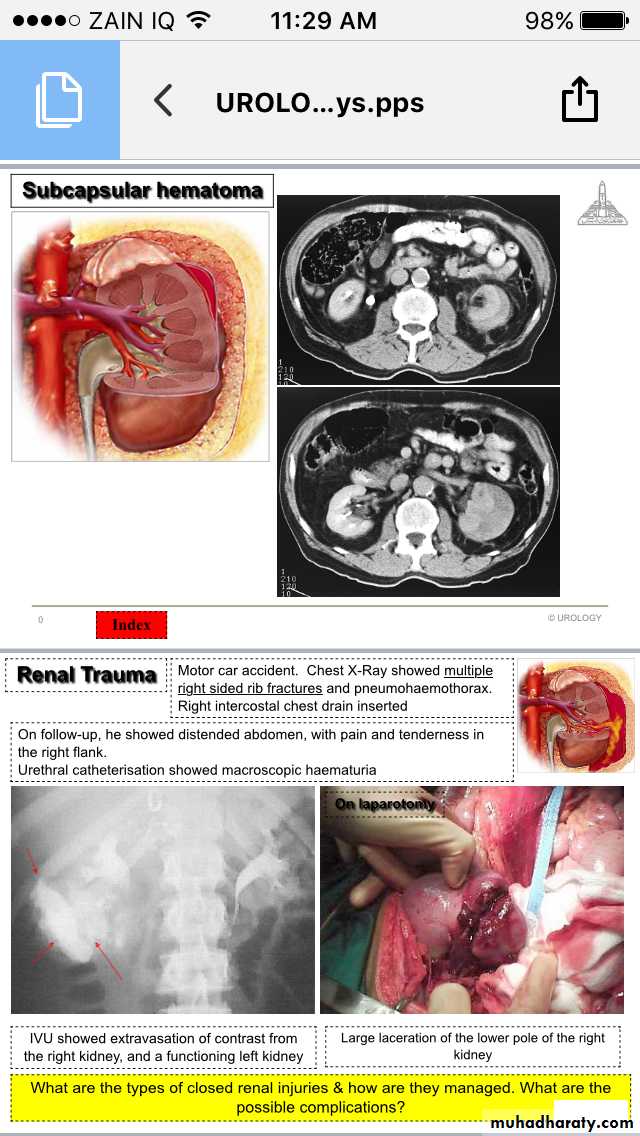

Trauma

Renal Injury